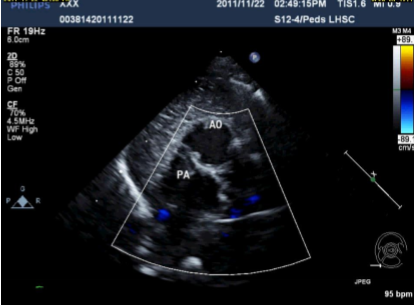

In PSSAX, the ventricles are side by side. This is diagnostic of…

L-TGA

Describe the findings of this image.

Aorta anterior and leftward of the PA.